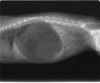

●胃捻転の正式名称は、英語でGastric Dilatation-Volvulusと言い、和訳では胃拡張-

胃軸捻転症である。獣医師間では略してGDVと言う。通常、人や猫では遭遇しない疾患である。

●空気を伴う劇的な胃の拡張があり、急変して来院する。そして、その殆どが捻転を伴っている。90~360度捻転するため、放置すれば、その程度により数時間内で死亡する。

●GDVは急性の、死が切迫した疾患であり、緊急処置を要する。早期の発見と治療開始が救命の基本である。胃拡張は胃の膨張のためであり、通常は嚥下した空気と胃内容物で充満される。胃拡張は胃軸捻転によって悪化する場合がある。

●GDVは胃がその長軸で捻転した時に起こり、これが胃からの流出の完全な閉塞をもたらす。同時に起こる胃-食道吻合部(噴門)の閉塞は嘔吐やおくびによる胃内のガスや内容物(胃内液体)の蓄積減少を不可能にする。

●症状は鼓腸を伴う腹囲膨満で、急性に発症する。嘔気を催すが、ガスや内容物の嘔吐を伴わない。その他に流涎、落ち着かない、呼吸困難などの症状がある。